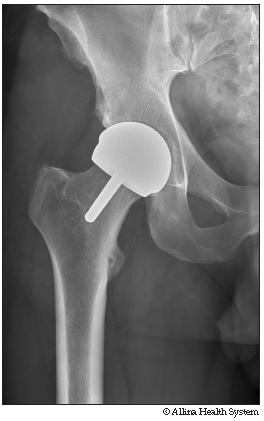

Hip resurfacing

An X-ray shows the artificial joint (prosthesis).

The hip after a hip resurfacing

Hip resurfacing removes the damaged cartilage from the hip joint. The surgeon replaces the damaged cartilage with an artificial joint (prosthesis).

The artificial joint is made of two polished metal surfaces that rub together with the help of the body's natural joint fluid. The metal surfaces provide a smooth joint for movement.

The upper thigh bone (femur) is capped with a metal prosthesis. A metal cup is placed in the pelvis to replace the worn socket. The pelvic side is placed without cement. The cap on the upper thigh bone (femur) is held in place with bone cement.